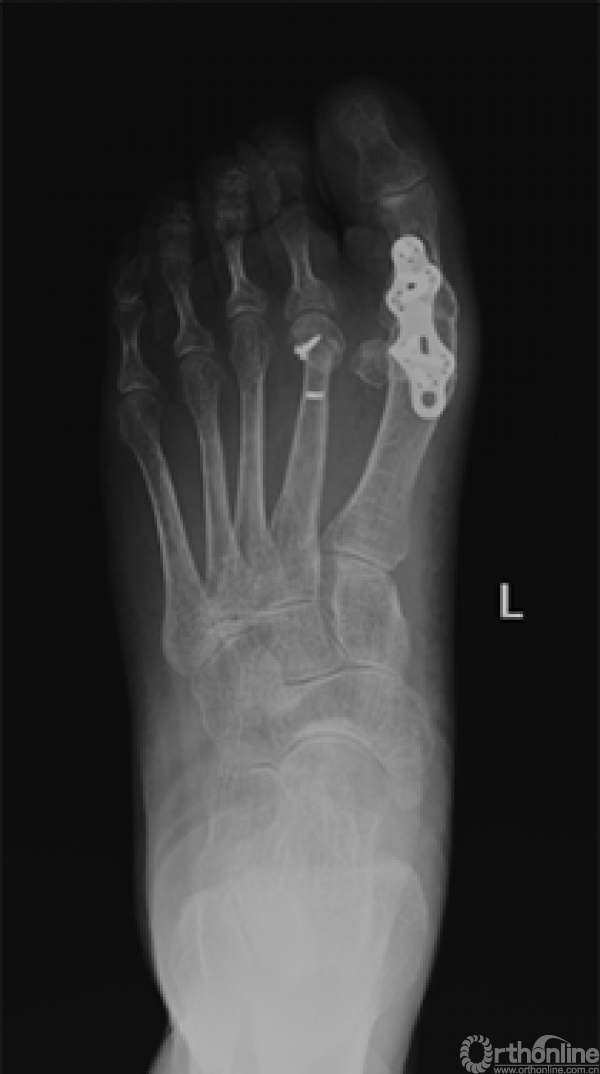

17、 术后X线

四、术后3个月随访